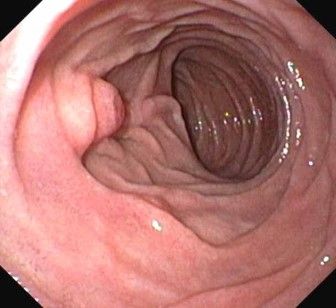

- Darmspiegelung / Sigmo – Kolo – Ileoskopie

Vorsorge Darmspiegelung / diagnostische Darmspiegelung

Präventive Koloskopie (Vorsorge Darmspiegelung)

Diagnostische Koloskopie zur Abklärung abdomineller Beschwerden, ggf. mit Probeentnahmen (z.B. bei Verdacht auf chronisch-entzündl. Darmerkrankung)